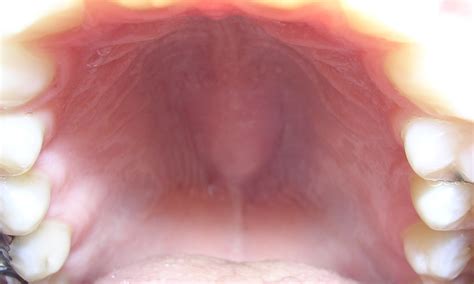

Torus mandibularis refers to a bony outgrowth, or exostosis, that develops along the lingual aspect (the side near the tongue) of the mandible, or lower jawbone. These growths are essentially dense, cortical bone covered by a thin layer of mucosal tissue. When browsing Torus Mandibularis images, you will typically observe that they appear as rounded, hard, and sometimes lobulated projections located above the mylohyoid line, usually in the area of the premolars.

Identifying these growths involves understanding their physical properties. Because they are composed of healthy, dense bone, they feel rock-hard to the touch and are immobile, as they are part of the jawbone itself. Here are the primary characteristics often depicted in Torus Mandibularis images:

• Location: Typically found on the lingual (tongue) side of the lower jaw, most commonly near the premolar teeth.

Visual Identification and Professional Diagnosis

While you may find many Torus Mandibularis images online that look remarkably similar to what you see in your own mirror, you should never attempt a self-diagnosis. What appears to be a torus could potentially be an abscess, an oral cyst, or another type of growth that requires a different treatment path. A dental professional uses a combination of clinical inspection and, if necessary, dental radiographs (X-rays) to confirm the diagnosis. Because tori are made of dense bone, they show up clearly as opaque, white masses on X-rays, allowing your dentist to distinguish them definitively from soft-tissue lesions.